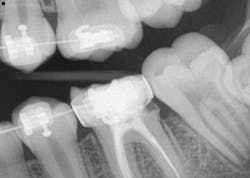

- Caries was clearly obvious around the fillings that were breaking down on Nos. 3 and 19. Its existence was definitely there prior to the placement of the orthodontic bands and wires. (It had only been four months!)

For the case presented here, thorough and detailed oral hygiene instructions were given by the hygienist, an electric toothbrush was suggested, and a four-month prophylactic rotation was recommended. Treatment entailed removing the bands and addressing the caries. Upon removal of the band on No. 19, there was very little tooth structure left. A new buildup with a stainless steel crown was placed. Due to the amount of leaking and lack of tooth structure, the patient’s mother was informed that the prognosis for the tooth was guarded.